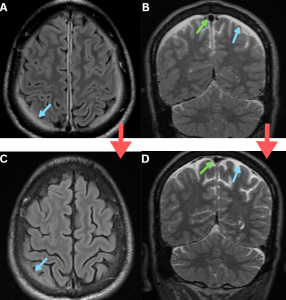

Fig 4: Figures A and B: Axial and coronal T2-weighted MR images demonstrating bilateral subdural hygromas (white arrows), seen as CSF-intensity fluid collections along the frontoparietal convexities.

Figures C and D: Axial and sagittal post-contrast T1-weighted images demonstrate diffuse smooth dural (green arrows) and tentorial (red arrow) enhancement over the bilateral cerebral hemispheres, consistent with pachymeningeal enhancement......Case 2—A patient with a chronic history of orthostatic headache, associated with neck stiffness and auditory symptoms, was evaluated for suspected spontaneous intracranial hypotension.

Figure E: Coronal T2-weighted MR image demonstrates a subdural collection along the left tentorium(blue arrow). {To our knowledge, tentorial subdural collection in spontaneous intracranial hypotension has not been previously described in the literature.}

Figure F: Axial T2/FLAIR MR image demonstrates dural thickening and hyperintensity along the brainstem and bilateral internal auditory canals(purple arrows).